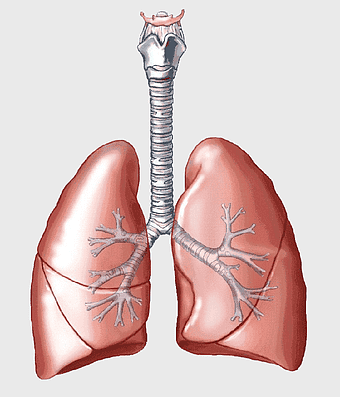

Lung Respiratory system, trachea and bronchus, pink lungs illustration, breathing anatomy, pulmonary health, respiratory function, medical education visuals -